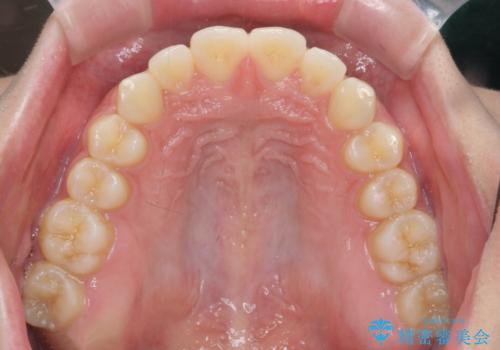

- 出っ歯のように見える前歯の角度を治したい、と矯正治療を希望され来院されました。

抜歯をせずにマウスピース矯正システムインビザラインを用いてしっかりと前歯の角度を改善していきます。

前歯の角度だけでなく内側に倒れ込んでいた奥歯もしっかり起こすことで咬合関係も理想的に仕上げています。